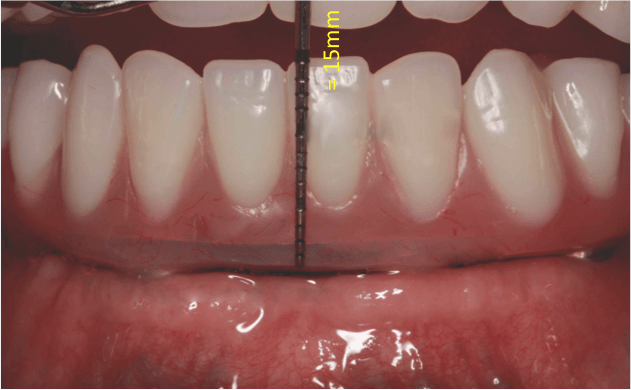

„All-on-4“ yra pažangi dantų implantavimo technika, leidžianti atkurti visą viršutinio arba apatinio žandikaulio dantų lanką vos su 4 implantais. Ant šių implantų fiksuojamas nuolatinis dantų protezas, kuris užtikrina ne tik estetišką šypseną, bet ir pilnavertę kramtymo funkciją. Šis metodas yra greitas, komfortiškas ir daugelio specialistų pripažįstamas kaip vienas efektyviausių sprendimų bedančiams žandikauliams netekus daugelio ar visų dantų.

- Dantų protezai ant 4 implantų vos per 24 – 48 val. Ir turite naujus visus dantis!